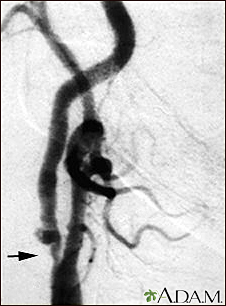

Carotid stenosis - X-ray of the right arteryBackCarotid stenosis - X-ray of the right arteryThis is an angiogram of the right carotid artery showing a severe narrowing (stenosis) of the internal carotid artery just past the carotid fork. There is enlargement of the artery or ulceration in the area after the stenosis in this close-up film. Note the narrowed segment toward the bottom of the picture. E-mail FormEmail ResultsName:Email address:Recipients Name:Recipients address:Message: